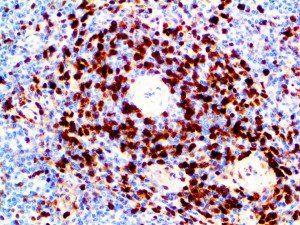

It is the ICU physician who is most likely to witness one of the deadliest manifestations of the abnormal immunological response, the cytokine storm syndrome (CSS). This response is also referred to by some as the cytokine release syndrome (CRS). CSS is characterized by continuous activation and expansion of macrophage and lymphocyte populations, which secrete large amounts of cytokines, causing the cytokine storm. This massive cytokine release is akin to hemophagocytic lymphohistiocytosis (HLH) disease, a syndrome characterized by initial unchecked and persistent activation of cytotoxic T lymphocytes and NK cells.

Clinical and laboratory manifestations of HLH include fever, enlarged liver and/or spleen, neurologic dysfunction, coagulopathy, liver dysfunction, cytopenias (i.e., low levels of erythrocytes, leukocytes, and/or platelets), hypertriglyceridemia, hyperferritinemia, hemophagocytosis, and eventually diminished NK cell activity as the immune system becomes progressively paralyzed. HLH can be familial (primary HLH) or secondary to another disease process (sHLH), such as rheumatic disease, in which it is referred to as macrophage activation syndrome (MAS, characterized by elevated ferritin).